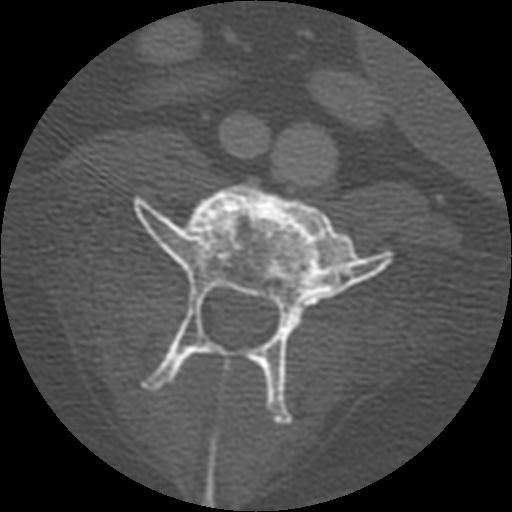

This week’s case is a 14-year-old female neutered Golden Retriever with progressive paresis of both hind limbs.

On the lateral radiograph, a large osteolytic site is present at the caudal aspect of the lamina of L4. This results in loss of the caudal half of the lamina and the articular facets of L4 with loss of the pedicles evident on the ventrodorsal projection. There is dural ossification in the cord. There is extensive ventral spondylosis throughout the lumbar vertebral column. No other sites of osteolysis are identified.

On the 1 mm, post contrast CT images, there is extensive osteolysis in L3 and L4 involving the vertebral bodies, laminae and dorsal spinous processes. There is a non contrast-enhancing soft tissue mass dorsal to the vertebrae.